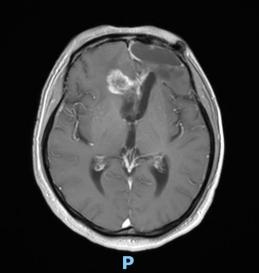

44歲的郭先生(化姓)為膠質(zhì)瘤復(fù)發(fā)患者,復(fù)查發(fā)現(xiàn)顱內(nèi)占位進(jìn)行性進(jìn)展1周,MRI檢查提示瘤體已累積到胼胝體,且瘤體位置較深,手術(shù)難度極高。面對這一挑戰(zhàn),王虎教授團(tuán)隊(duì)決定采用多種先進(jìn)技術(shù)輔助手術(shù),其中最為引人注目的就是首次引入的細(xì)胞級顯微鏡EndoSCell?。該設(shè)備是目前全球唯一實(shí)時(shí)在體細(xì)胞級顯影的儀器,可以輔助醫(yī)生從細(xì)胞層面區(qū)分腫瘤組織與正常組織,從而做到細(xì)胞級精準(zhǔn)切除。

患者術(shù)前核磁影像

整個(gè)手術(shù)過程在“腦醫(yī)匯”平臺進(jìn)行了全程直播,吸引了近千位神經(jīng)外科領(lǐng)域的專家學(xué)者觀看,他們紛紛對王虎教授團(tuán)隊(duì)的精湛技藝和EndoSCell?的先進(jìn)技術(shù)表示贊賞。術(shù)后,患者的生命體征平穩(wěn),CT及MRI檢查顯示腫瘤切除滿意,無明顯出血和并發(fā)癥。患者神志清醒,精神狀態(tài)良好,目前恢復(fù)良好。